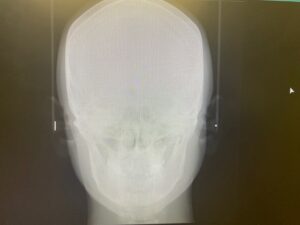

② レントゲン(正面セファロ・側面セファロ・パノラマ)